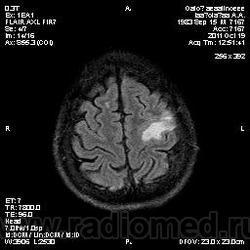

Колеги, спасибо за высказывания. В данном случае про наркоманский анамнез указано не спроста... Есть мнение, что в этом лежит точка отсчета.... По поводу абсцесса и гематомы - не согласен; по поводу первого - нет соответствющей клиники, по поводу второго - не характерна локализация и сигнальные характеристики. Не буду томить общественность касательно собственного мнения. Есть две гипотезы, о которых думается в данном случае: прогрессирующая лейкоэнцефалопатия и новообразование... Но без контраста их не разрешить...

пожалуй "первое", но в отношении "второго"смущает "круглит" на вершине "воспалительной демиелинизации", который она (демиелинизация) так странно обходит...

Имеются  в виду последние 2 картинки?Мне тоже так показалось.А почему контрастирования не будет?Чем контрастируете?